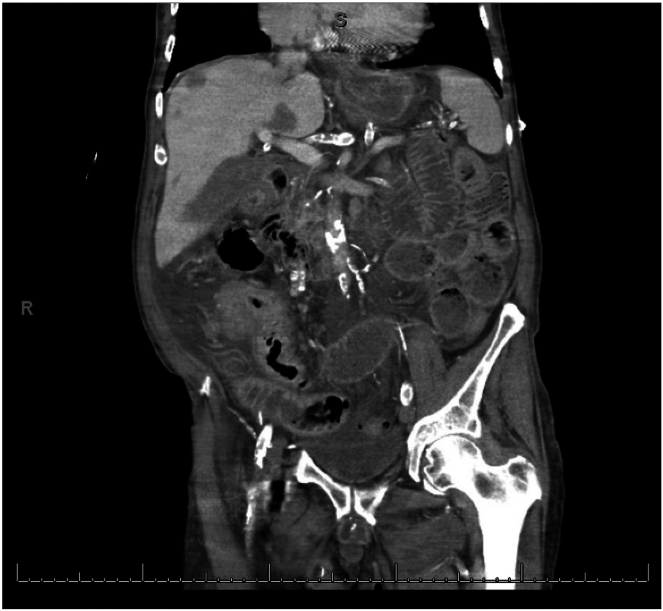

Malignant bowel obstruction is a challenging complication in advanced gastrointestinal malignancies with varying treatment strategies including medical, surgical and endoscopic therapies, each with their own limitations. Endoscopic ultrasound–guided enterocolostomy has been previously reported as an option for patients who are not surgical candidates or ideal candidates for enteral stenting. In this case, endoscopic ultrasound–guided enterocolostomy is used for the palliation in a patient with a completely obstructing large cecal adenocarcinoma who declined surgical intervention.